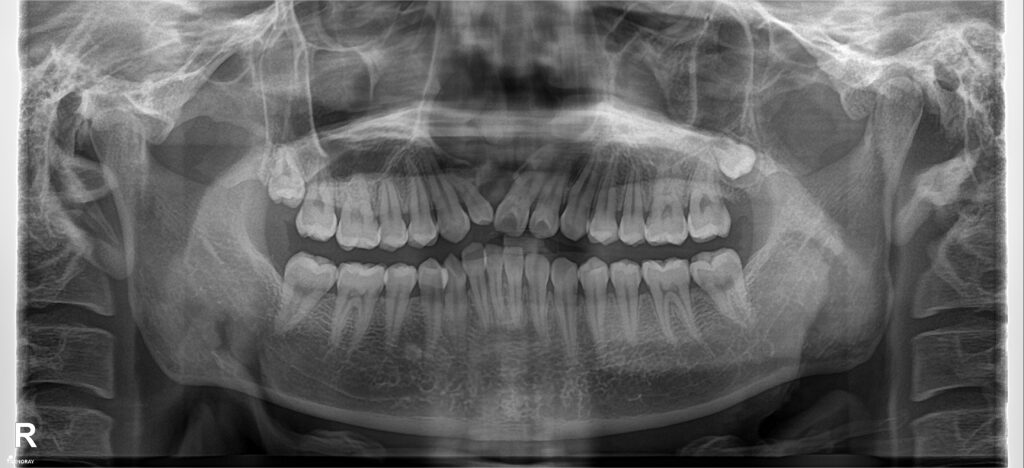

Đây là 1 case BN khe hở môi thiếu R11 bẩm sinh, trước điều trị là tình trạng hẹp hàm trên, cắn ngược hàm trên nghiêm trọng.

Bệnh nhân được giải cắn ngược, tạo khoảng phục hình R11. Kết thúc tháo niềng sau 1.5 năm điều trị